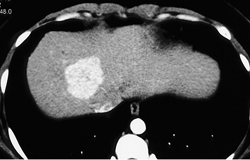

Focal Nodular Hyperplasia (FNH)